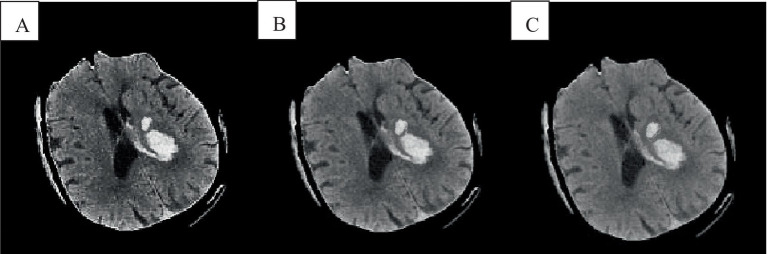

Abstract Image

In recent years, intracerebral hemorrhage (ICH) has garnered significant attention as a severe cerebrovascular disorder. To enhance the accuracy of ICH detection and segmentation, this study proposed an improved fuzzy C-means (FCM) algorithm and performed a comparative analysis with both traditional FCM and advanced convolutional neural network (CNN) algorithms. Experiments conducted on the publicly available CT-ICH dataset evaluated the performance of these three algorithms in predicting ICH volume. The results demonstrated that the improved FCM algorithm offered notable improvements in computational time and resource consumption compared to the traditional FCM algorithm, while also showing enhanced accuracy. However, it still lagged behind the CNN algorithm in areas such as feature extraction, model generalization, and the ability to handle complex image structures. The study concluded with a discussion of potential directions for further optimizing the FCM algorithm, aiming to bridge the performance gap with CNN algorithms and provide a reference for future research in medical image processing.